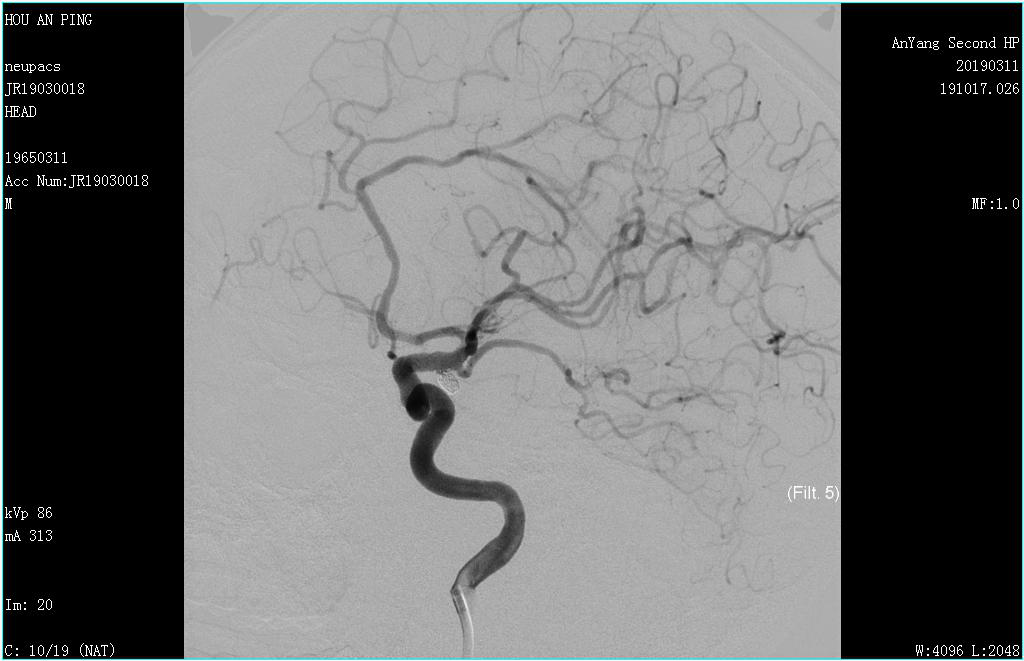

團隊人員及時(shí)將造影結果與患者家屬溝通,建議行顱內動(dòng)脈瘤栓塞術(shù),家屬商量后再決定。然而時(shí)間不等人,病情不能耽誤,每增加一秒病人就需承受動(dòng)脈瘤破裂的巨大風(fēng)險,在家屬商量的同時(shí)陳醫師迅速聯(lián)系上級醫院專(zhuān)家,專(zhuān)家組明確了腦血管動(dòng)脈瘤栓塞的治療計劃。當患者家屬商量后同意治療方案時(shí),我們的神經(jīng)內科介入團隊已與專(zhuān)家組確定了治療方案和治療時(shí)間,在醫療科協(xié)調指揮下,多學(xué)科協(xié)作,麻醉科、器械科都及時(shí)到位。次日17:30,專(zhuān)家到達,再次造影后于全麻下行主動(dòng)脈弓+全腦血管造影術(shù)+經(jīng)股動(dòng)脈支架輔助下顱內動(dòng)脈瘤栓塞術(shù)。導絲在路途指引下小心置于動(dòng)脈瘤瘤腔內,經(jīng)微導管依次填入彈簧圈,1個(gè)、2個(gè)、3個(gè)...,填入第8個(gè)彈簧圈時(shí)釋放困難,病人瘤頸寬,擬行支架輔助下動(dòng)脈瘤栓塞,將支架準確釋放于動(dòng)脈瘤瘤頸處,釋放最后一個(gè)彈簧圈,填塞過(guò)程順利,造影顯示瘤腔栓塞致密,動(dòng)脈瘤瘤腔未見(jiàn)造影劑顯影,載瘤動(dòng)脈前向血流良好,手術(shù)過(guò)程順利,家屬長(cháng)松了一口氣,為表達感激之情,特意給陳醫師及文主任包了兩個(gè)2000元的紅包,兩位醫師婉拒,并及時(shí)制定下一步治療方案,因為這場(chǎng)仗,還沒(méi)到吹響勝利號角的時(shí)候。接下來(lái)病人要面臨吸收熱、癲癇、腦血管痙攣、下肢靜脈血栓等風(fēng)險。